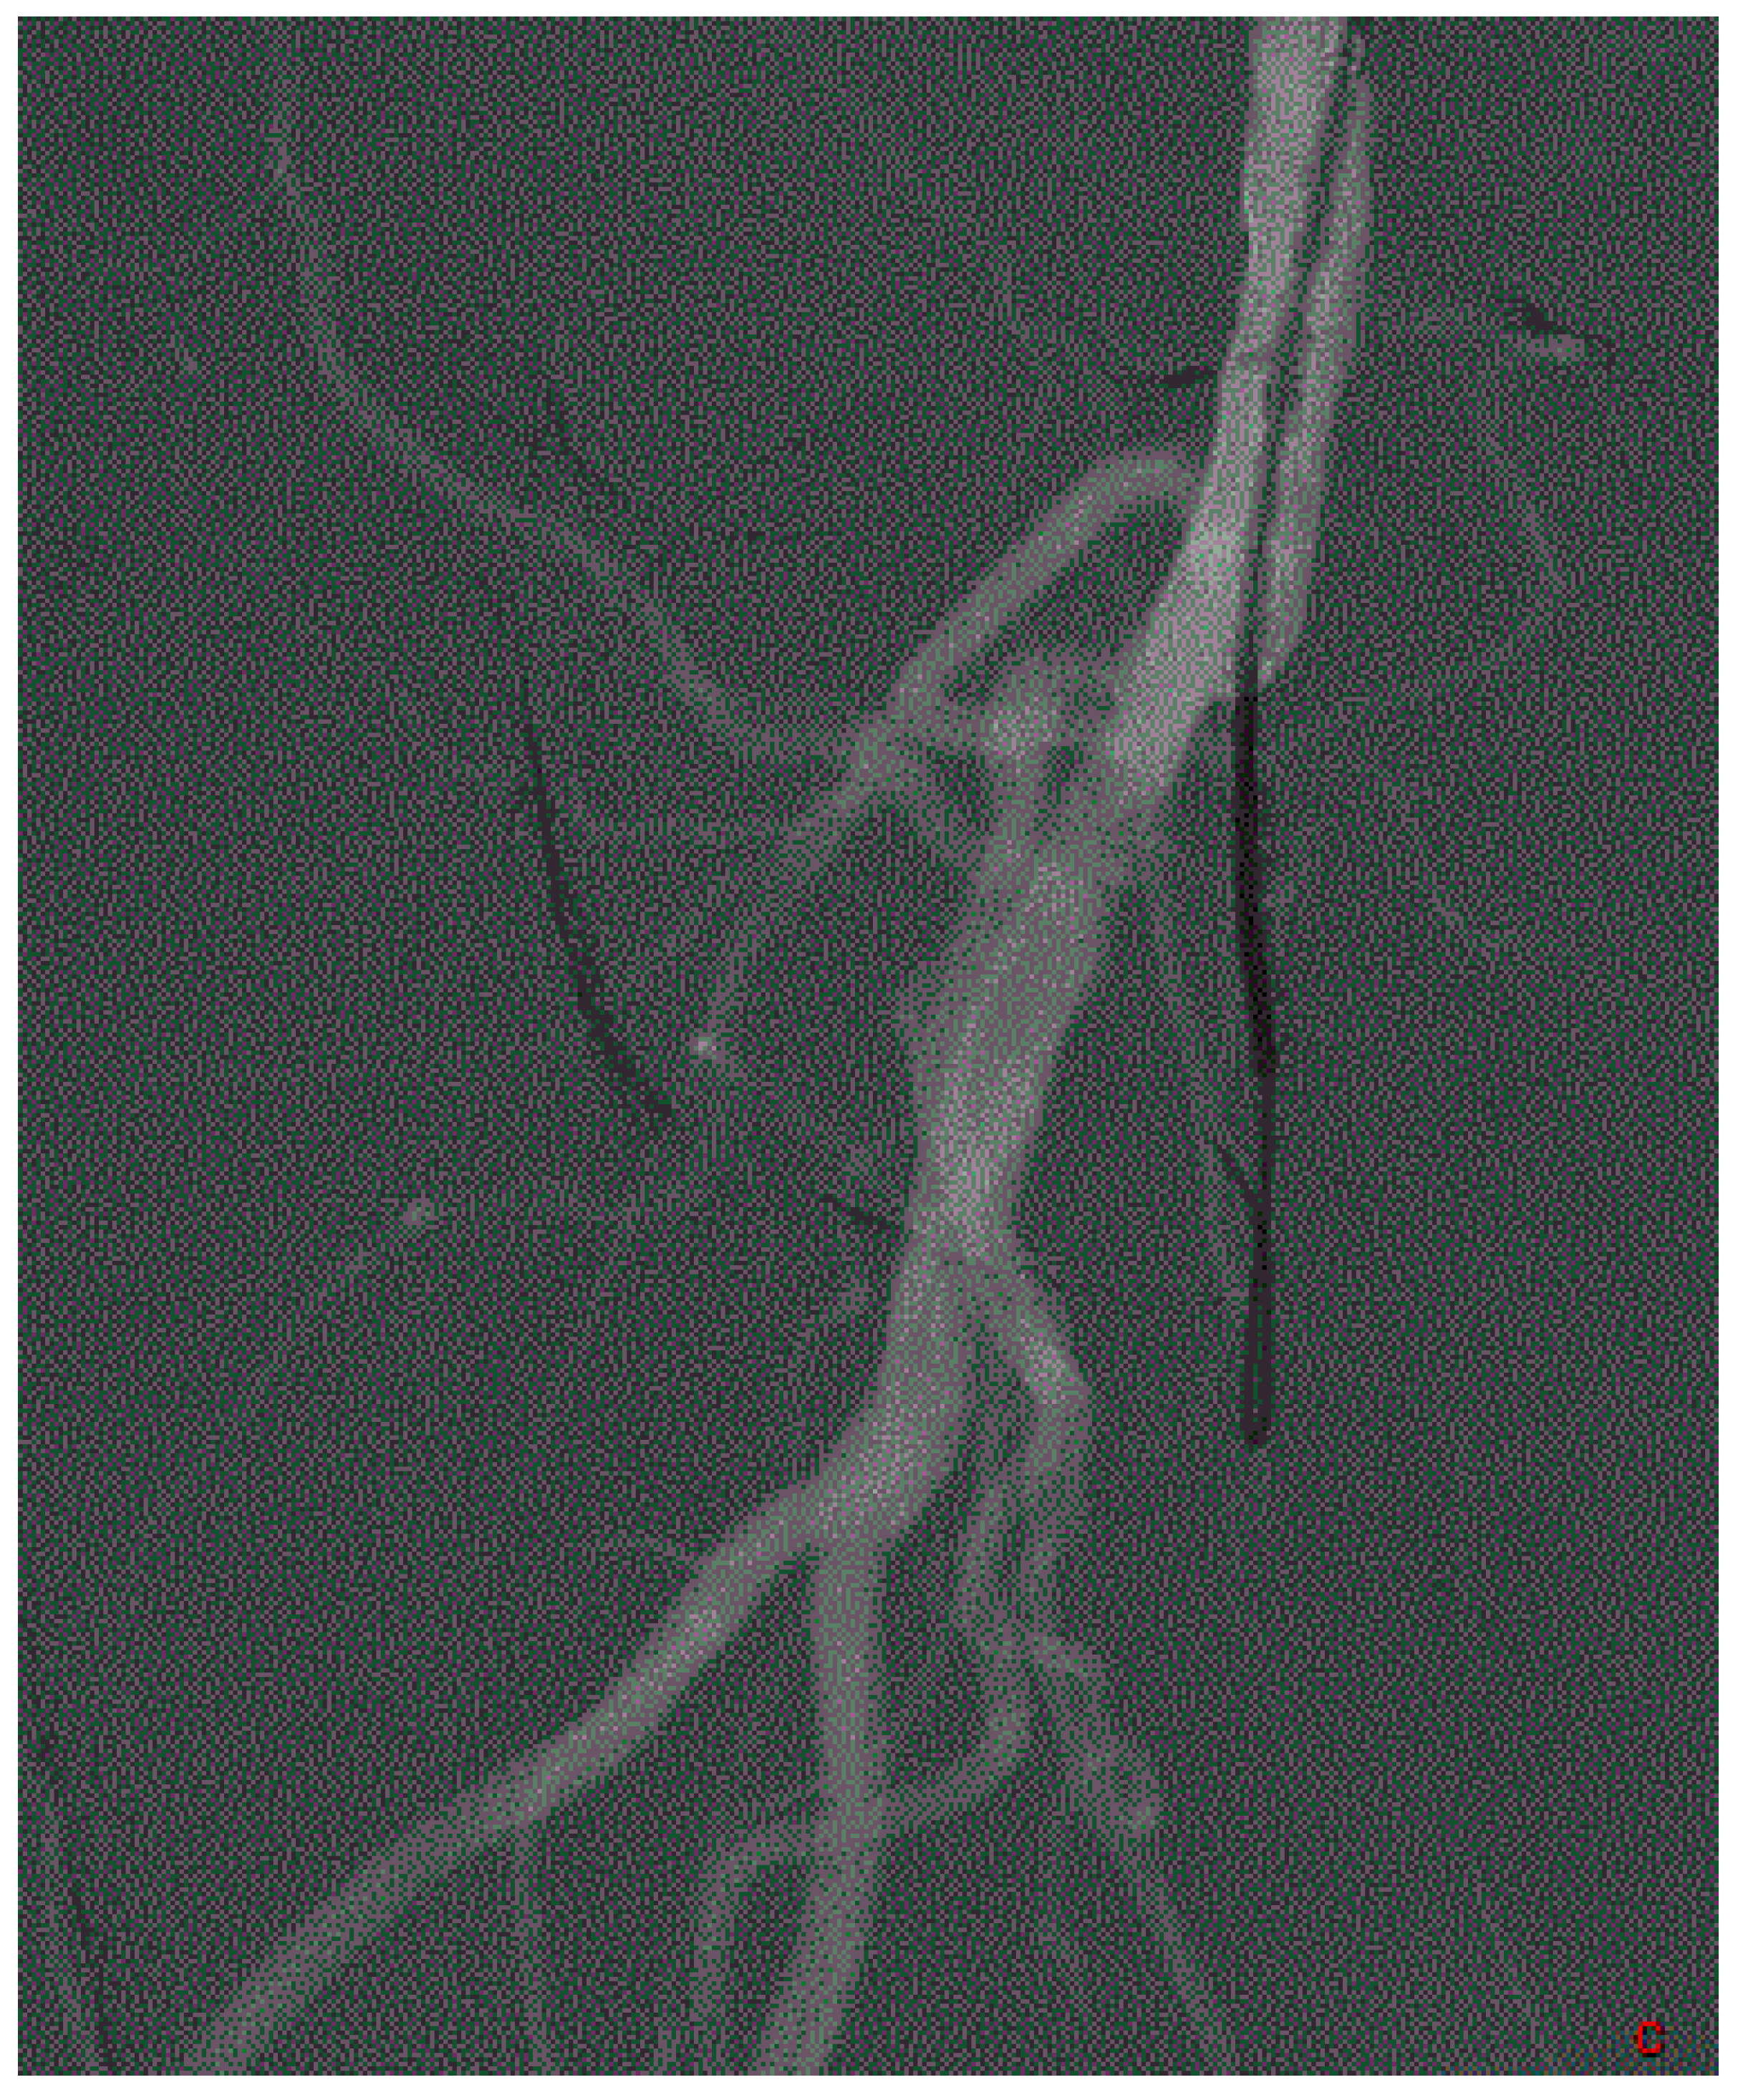

2. Define the Approach

3. Crossing the Lesion

4. Arterial Lesion Preparation